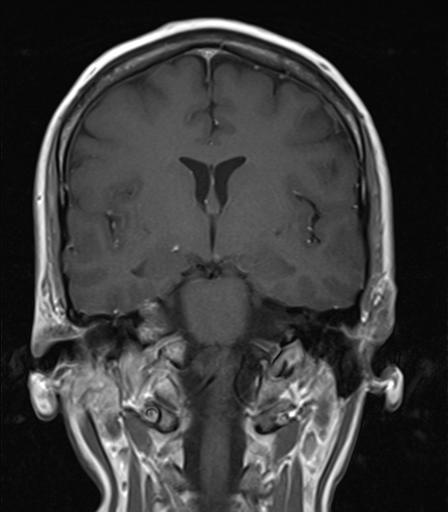

MRI August 2010.

Diagnose: There is no evidence to suspect that this patient may have an active phase of disease.